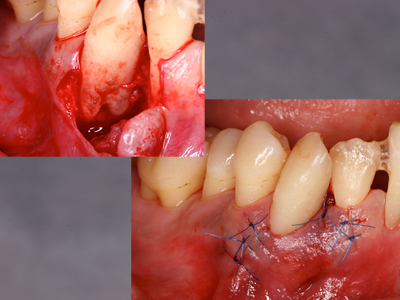

侵襲性歯周炎治療経過その3です。

右下3のみすっきりせず、レントゲン上で何やら怪しい像、、、

フラップをあけてみると、犬歯なのに複根、そこまで骨吸収が進んでいました。

こんなときこそ再生療法の適応なのかもしれません。